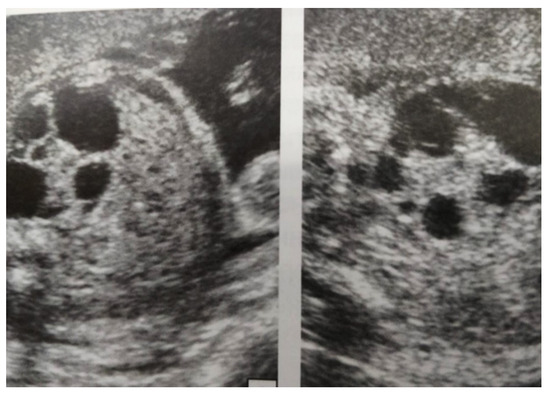

Figure 4. Ultrasound at 31st week of gestation. Bilateral hydrocalconephrosis.

Our experience with congenital malformations of the urinary system refers to the following clinical case (Figure 2, Figure 3, Figure 4, Figure 5, Figure 6, Figure 7, Figure 8 and Figure 9). In the first case, during pregnancy, the 21-week ultrasound determined bilateral renal pyelectasia. The fetus had hydronephrosis on the right; at 31 weeks, it had bilateral hydrocalconephrosis; and at 32 weeks, bilateral pyelectasia. It suffered premature birth at 36 weeks, with complicated anomalies of the forces of contraction, prolonged birth, and birth weight of 2200 g. Postnatal ultrasonography was supplemented by intravenous urography, and bilateral hydronephrosis was determined. Hydrocalconephrosis on the left was discovered. The complete diagnosis was established: congenital renal malformation; bilateral pyelectasia; bilateral hydronephrosis; hydrocalconephrosis on the left; and severe reduced glomerular filtration rate (GFR), GFR > 2SD below mean.